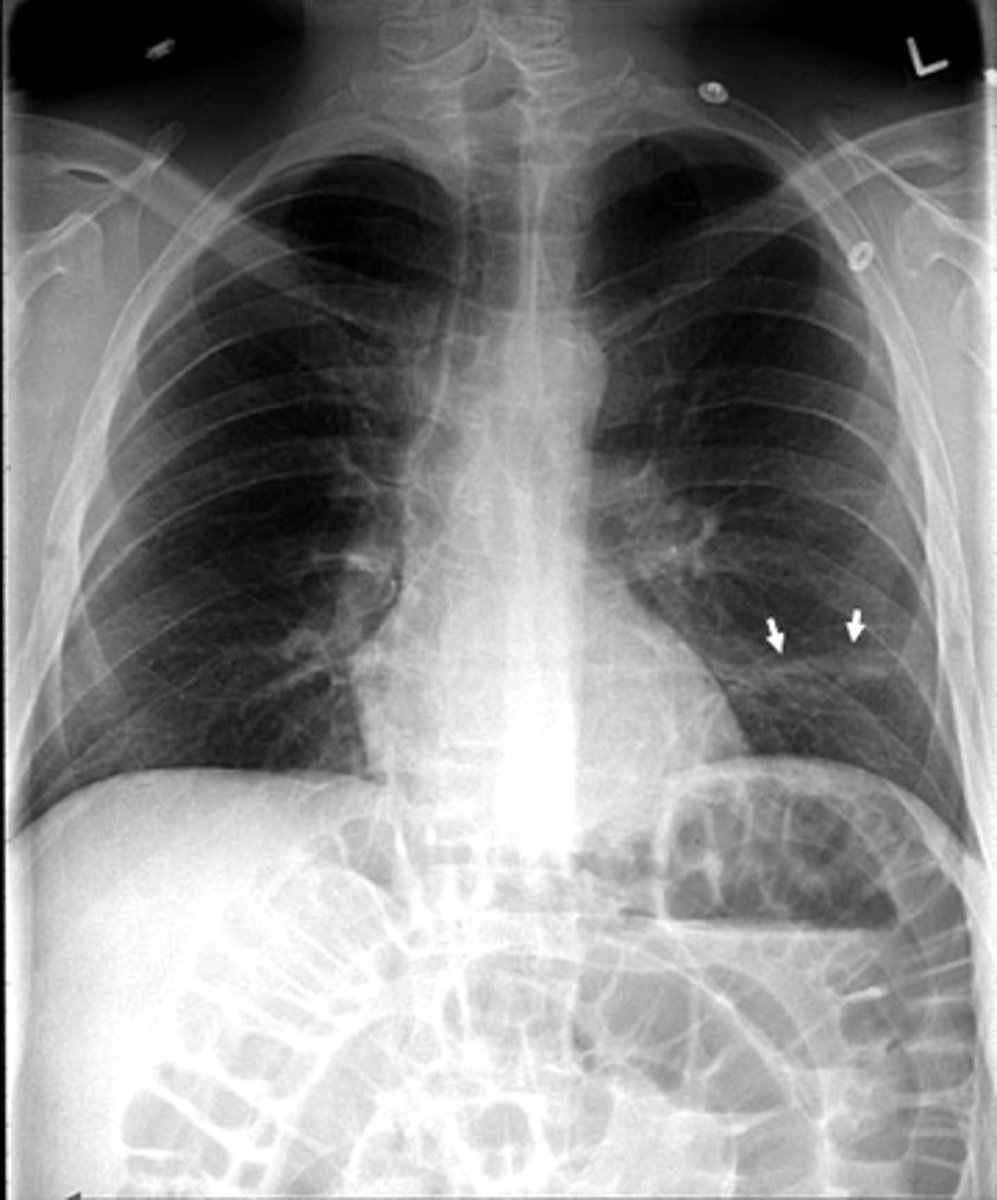

Pleural effusion

knowt flashcard image

Pleural effusion (right sided)